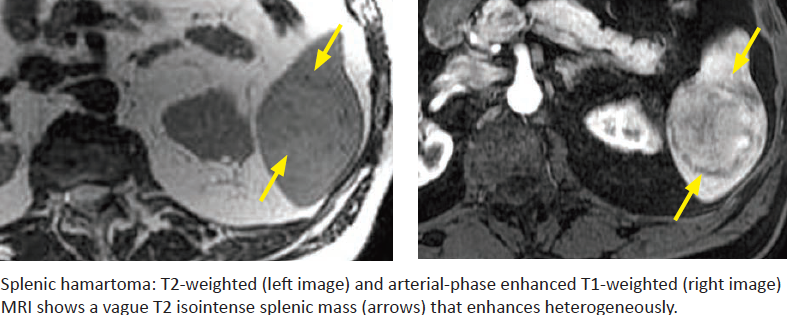

Splenic Hamartoma

What is it? Possible association?

Imaging appearance?